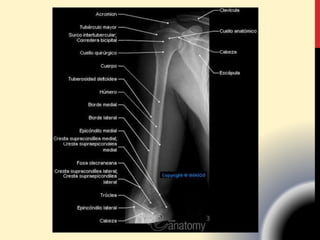

1. HÚMERO

CABEZA:

• Superficie articular lisa y redondeada.

• La porción rugosa y más o menos

estrechada que limita el perímetro de

la cabeza se llama CUELLO

ANATÓMICO.

1.1. EXTREMO

SUPERIOR.

Por fuera de la mitad superior del cuello

anatómico se distinguen 2 eminencias:

• Una pequeña y anterior llamada TROQUIN

(tuberosidad menor). M. Subescapular.

• A partir de este sigue un trayecto descendente

se conoce como CRESTA SUBTROQUINIANA

(cresta del tubérculo menor)

1.1. EXTREMO SUPERIOR.

• Una de mayor mas voluminosa es el TROQUITER

(tuberosidad mayor) y la CRESTA SUBTROQUITERIANA

(CT mayor).

• Inserciones :

• Tendon M.supraespinoso,

• M. infraespinoso y

• M. redondo mayor.

TUBEROSIDADES:

Entre el troquin y troquiter existe un canal de

dirección vertical llamado CORREDERA BICIPITAL

(surco intertubercular) por allí transcurre el tendón

de la porción larga del bíceps braquial.

La zona por debajo de los

tubérculos :

• CUELLO QUIRÚRGICO (Metafisis)

(une el cuerpo con las

extremidades).

• Crecimiento y fracturas

Es rectilineo pero parece torcido

sobre su eje.

En la parte inferior adopta la

forma de un prisma.

Tiene 3 bordes y 3 caras.

1.2. CUERPO

Extremo inferior del húmero:

• FOSAS CORONOIDEAS

• FOSA RADIAL

• CONDILO ( EPICONDILO )

• TROCLEA (EPITROCLEA )

• CRESTAS SUPRACONDILEAS

• FOSA OLECRANEANA

Cara postero inferior:

Presenta un surco liso

• CANAL EPITROCLEO OLECRANEANO para el

nervio cubital.

• El canal RADIAL o de torsión.

Cara antero externa:

• Presenta la impresión VDELTOIDEA.

• M. deltoides (por su lado superior),

• M.braquial anterior (por su lado inferior).

1.2. CUERPO: